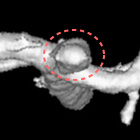

脳動脈瘤塞栓術

脳動脈瘤が破裂して出血するのを防ぐために、脳動脈瘤にコイルを詰めて血液が入り込まないようにする手術です。

術後に血管撮影を行うと、コイルで置き換わった脳動脈瘤は造影剤が入らないため描出されなくなります。